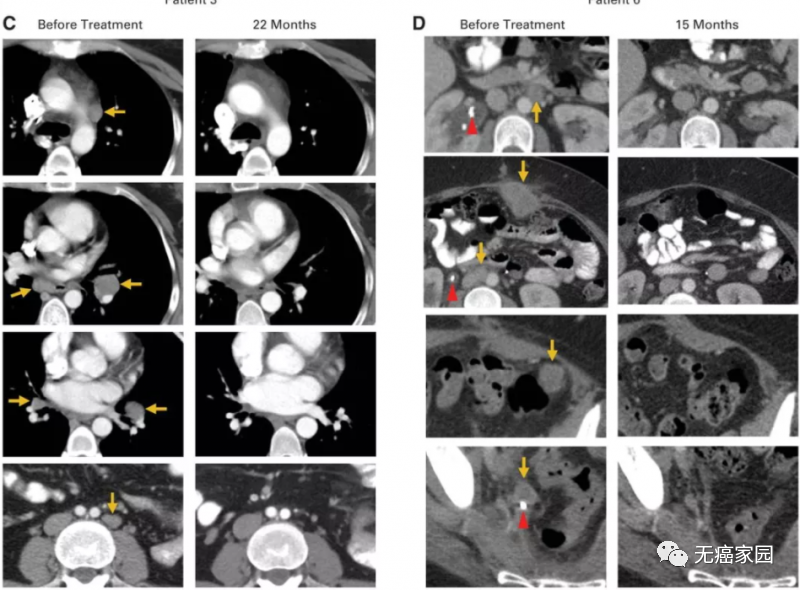

经过1个月治疗后,她回去接受胸部、腹部和骨盆的 CT 扫描以及肝脏的 MRI 扫描。Hinrichs 告诉她,肿瘤明显缩小了。特别是,她腹部的肿瘤在扫描中已经检测不到。

治疗2个月后,Scott的复查结果再次震惊众人,影像学检查显示,她的体内已经没有任何癌症的迹象。2015年5月,Hinrichs博士第一次将他参与的这项临床试验的初期结果在肿瘤会议上公布,9名患者中的Scott和Aricca Wallace女士的转移性肿瘤全部消失了,完全缓解时间已超过两年。